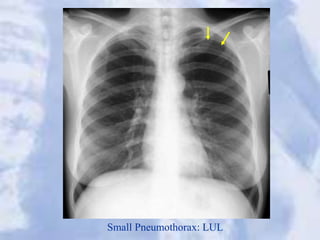

Small Pneumothorax: LUL